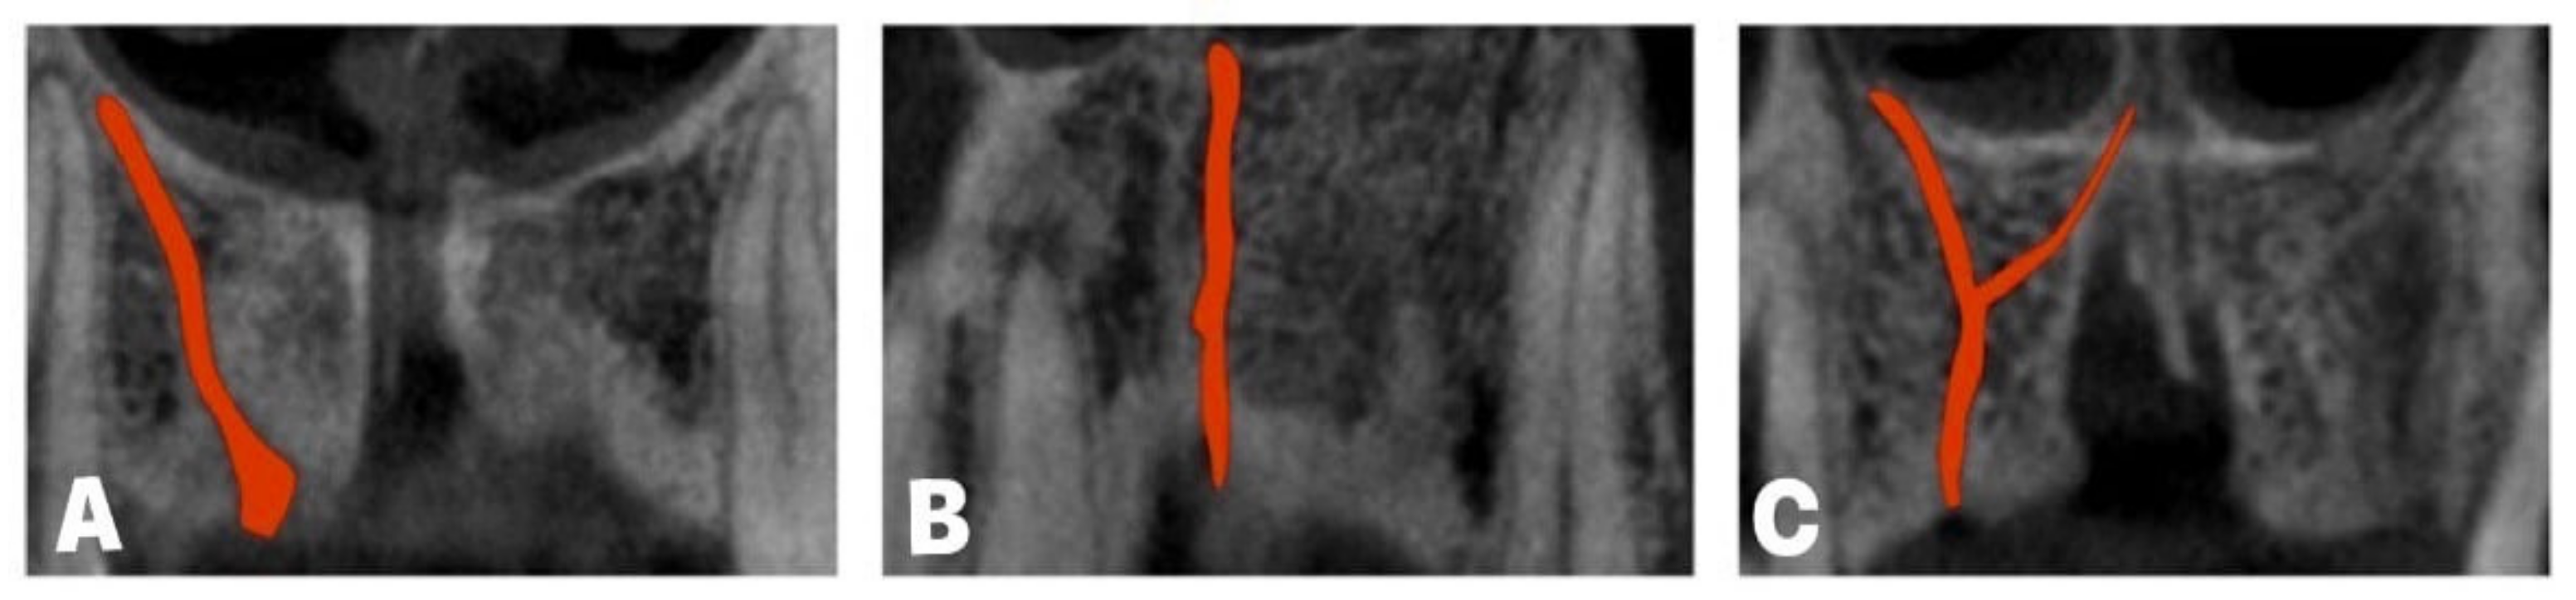

- Vasiljevic, M.; Milanovic, P.; Jovicic, N.; Vasovic, M.; Milovanovic, D.; Vojinovic, R.; Selakovic, D.; Rosic, G. Morphological and Morphometric Characteristics of Anterior Maxilla Accessory Canals and Relationship with Nasopalatine Canal Type-A CBCT Study. Diagnostics 2021, 11, 1510. [Google Scholar] [CrossRef] [PubMed]

- Baena-Caldas, G.; Rengifo-Miranda, H.; Heerera-Rubio, A.; Peckham, X.; Zúñiga, J. Frequency of canalissinuosus and its anatomic variations in cone beam computed tomography images. Int. J. Morphol. 2019, 37, 852–857. [Google Scholar] [CrossRef]

- Machado, V.C.; Chrcanovic, B.R.; Felippe, M.B.; Manhães Júnior, L.R.; de Carvalho, P.S. Assessment of accessory canals of the canalissinuosus: A study of 1000 cone beam computed tomography examinations. Int. J. Oral Maxillofac. Surg. 2016, 45, 1586–1591. [Google Scholar] [CrossRef] [PubMed]

- Von Arx, T.; Lozanoff, S.; Sendi, P.; Bornstein, M.M. Assessment of bone channels other than the nasopalatine canal in the anterior maxilla using limited cone beam computed tomography. Surg. Radiol. Anat. 2013, 35, 783–790. [Google Scholar] [CrossRef] [PubMed]

- Tomrukçu, D.N.; Köse, T.E. Assesment of accessory branches of canalissinuosus on CBCT images. Med. Oral Patol. Oral Cir. Bucal. 2020, 25, e124–e130. [Google Scholar] [CrossRef] [PubMed]

- Wanzeler, A.M.; Marinho, C.G.; Alves Junior, S.M.; Manzi, F.R.; Tuji, F.M. Anatomical study of the canalissinuosus in 100 cone beam computed tomography examinations. Oral Maxillofac. Surg. 2015, 19, 49–53. [Google Scholar] [CrossRef] [PubMed]